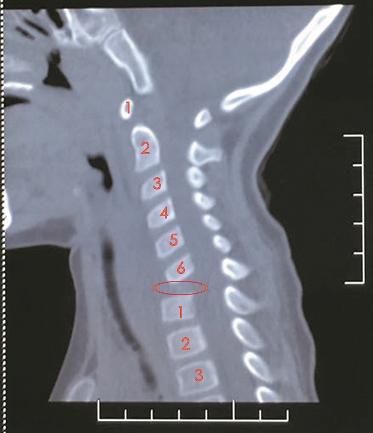

頸椎CT:紅圈所在位置為琦琦缺失的頸7椎體。

到底怎么回事?琦琦被送到醫(yī)院檢查,結(jié)果讓人大吃一驚,琦琦患上的是“頸椎結(jié)核”!影像學檢查發(fā)現(xiàn)她頸7椎體周圍有大量膿腫,而且那一節(jié)頸椎的骨質(zhì)已被結(jié)核桿菌吞噬得“面目全非”,就好像“消失”了一樣。